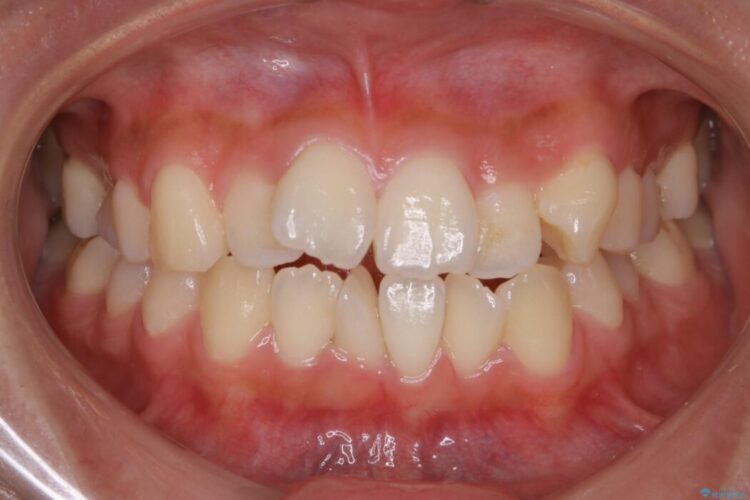

上下前歯のねじれなどで生じている歯列のガタつきをなおしたいとのことで来院されました。

特に前歯部分に90度近く捻転した歯、斜めに生えている歯などによる歯列のがたつき、正中のズレが目立っていました。